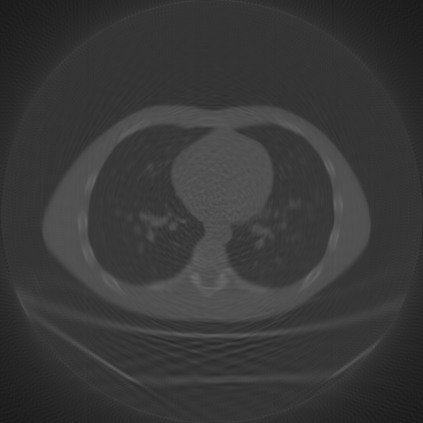

Sparse-view computed tomography (CT) is known as a widely used approach to reduce radiation dose while accelerating imaging through lowered projection views and correlated calculations. However, its severe imaging noise and streaking artifacts turn out to be a major issue in the low dose protocol. In this paper, we propose a dual-domain deep learning-based method that breaks through the limitations of currently prevailing algorithms that merely process single image slices. Since the scanned object usually contains a high degree of spatial continuity, the obtained consecutive imaging slices embody rich information that is largely unexplored. Therefore, we establish a cascade model named LS-AAE which aims to tackle the above problem. In addition, in order to adapt to the social trend of lightweight medical care, our model adopts the inverted residual with linear bottleneck in the module design to make it mobile and lightweight (reduce model parameters to one-eighth of its original) without sacrificing its performance. In our experiments, sparse sampling is conducted at intervals of 4{\deg}, 8{\deg} and 16{\deg}, which appears to be a challenging sparsity that few scholars have attempted before. Nevertheless, our method still exhibits its robustness and achieves the state-of-the-art performance by reaching the PSNR of 40.305 and the SSIM of 0.948, while ensuring high model mobility. Particularly, it still exceeds other current methods when the sampling rate is one-fourth of them, thereby demonstrating its remarkable superiority.